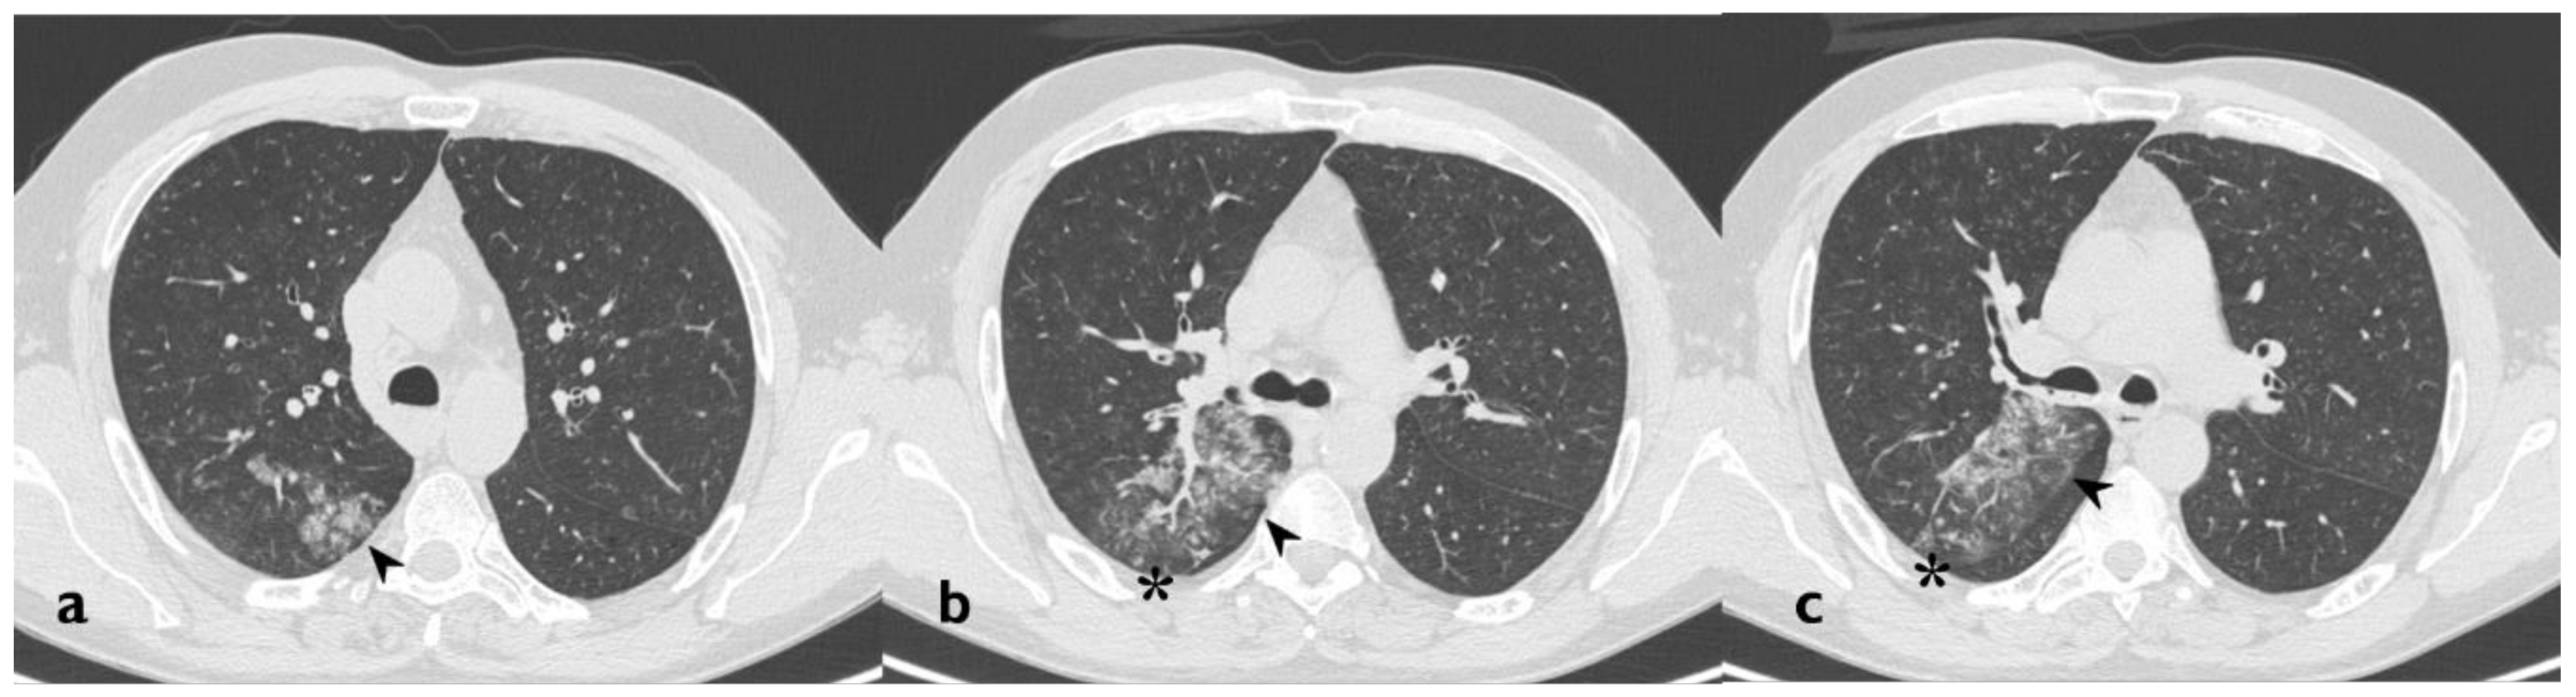

| HRCT Pattern | Associated Drugs |

|---|---|

| Fibrotic pattern | Nitrofurantoin (chronic toxicity), methotrexate, sulfalazina, rituximab, tocilizumab, bleomycin, busulfan, cyclophosphamide (chronic toxicity), amiodarone (form with fibrous course), tocainide, cocaine |

| Organizing pneumonia | Nitrofurantoin (chronic toxicity), methotrexate |

| Mosaic pattern | Nitrofurantoin (acute toxicity), methotrexate, sulfalazina |

| Isolated ground glass | Rituximab, tocilizumab, cyclophosphamide (acute reaction), amiodarone (initial stage), cocaine |

| Alveolar hemorrhage | Penicillamine, rituximab, cocaine |

| Pulmonary edema | Acetyl-salicylic acid, mitomycin |

| Pleural effusion | Sulfonamides, methotrexate |